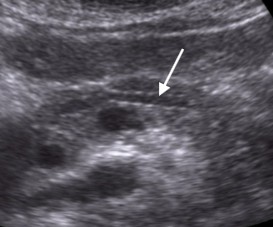

What does the white arrow point to?

Duct of wirsung

What does the white arrow point to?

Duct of wirsung